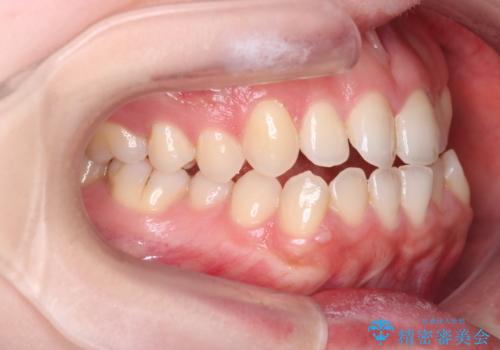

【インビザライン】オープンバイトを治したい

- 前歯の凸凹を主訴に来院された患者様です

骨格性の下顎前突傾向もあったため、臼歯関係の遠心移動も行うことで綺麗な仕上がりで矯正を終了することができました。

遠心移動を行うことで期間はかかりましたが、良い状態で仕上がっています。